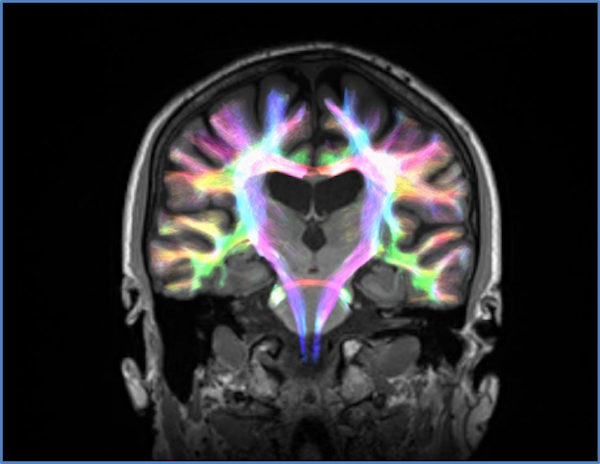

Utilizamos um método avançado de imagem cerebral, chamado IRM por difusão, que nos permitiu visualizar a estrutura das conexões entre as diferentes regiões cerebrais envolvidas nesses circuitos. Usando essa tecnologia, podemos quantificar se a força dessas conexões foi afetada pela doença de Parkinson.

| Usamos imagens de difusão para estudar a atividade cerebral dos participantes. Autor fornecido |